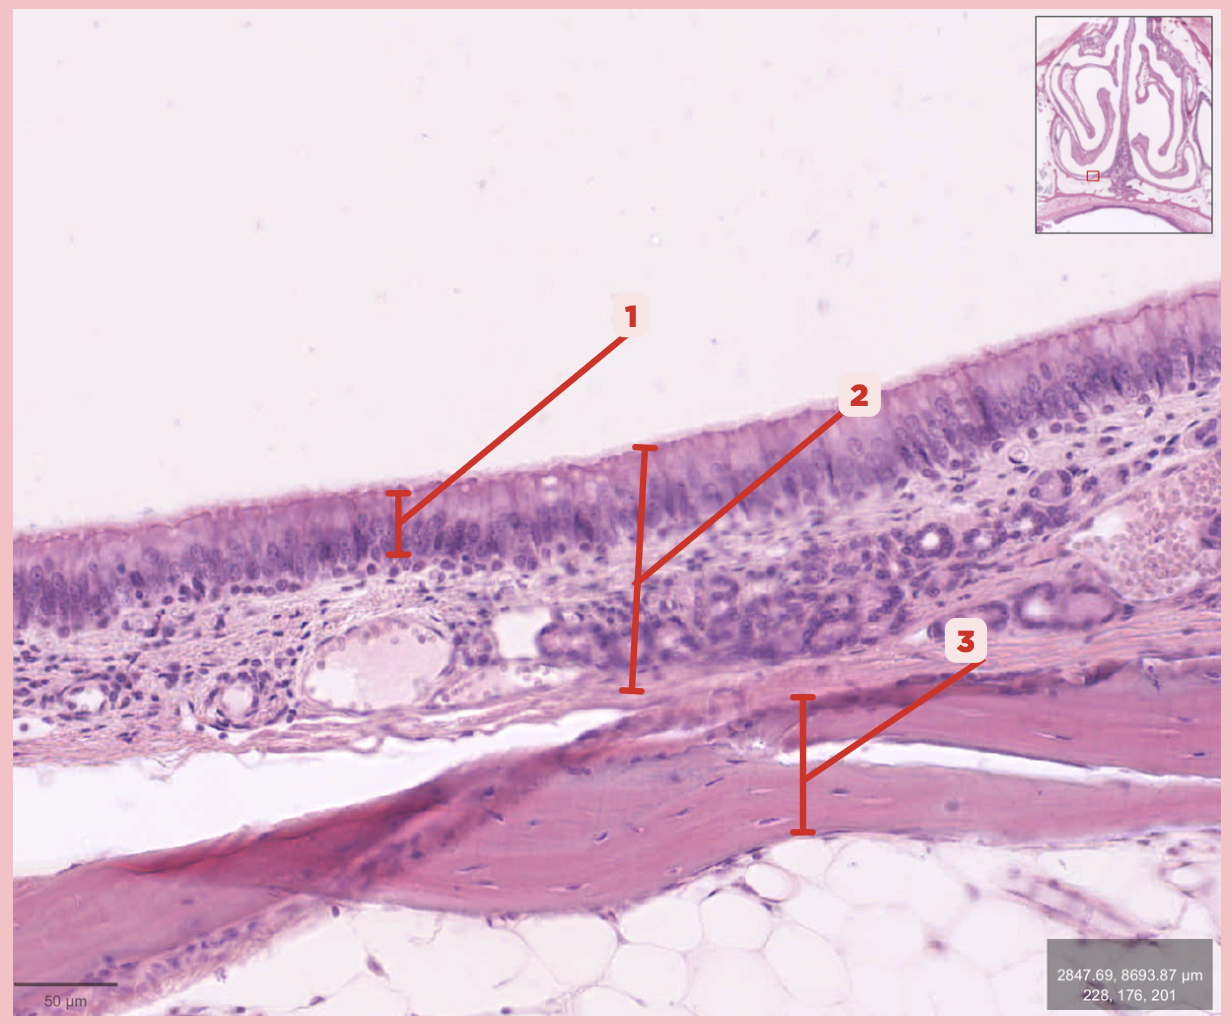

Respiratory Epithelium

Identify the structure labeled as 1.

Mucosa

Identify the structure labeled as 2.

Bone

Identify the structure labeled as 3.

Keratinized stratified squamous epithelium

What’s the lining epithelium at #3?

No

Are Glands present at #1?

Lamina Propria

Identify the structure labeled as 1.

Adipocytes

Identify the structure labeled as 2.

Keratinized stratified squamous epithelium

Identify the structure labeled as 3.